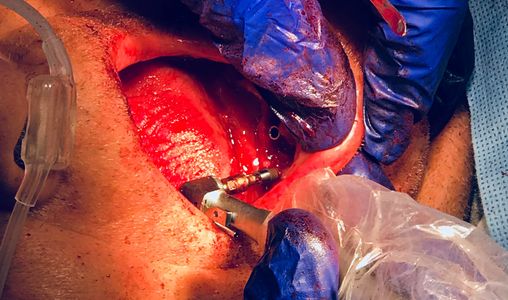

After Dr. Gibney drills holes using the surgical guide, he removes the guide. He uses a drill to place implant posts to the left.

To the right, Dr. Gibney uses a hammer to place an implant post.